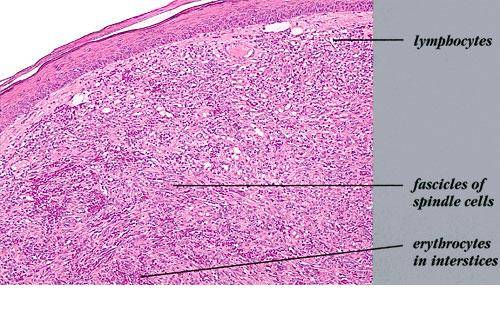

Kaposi’s sarcoma

What is Kaposi Sarcoma?

Kaposi's sarcoma

Kaposi Sarcoma